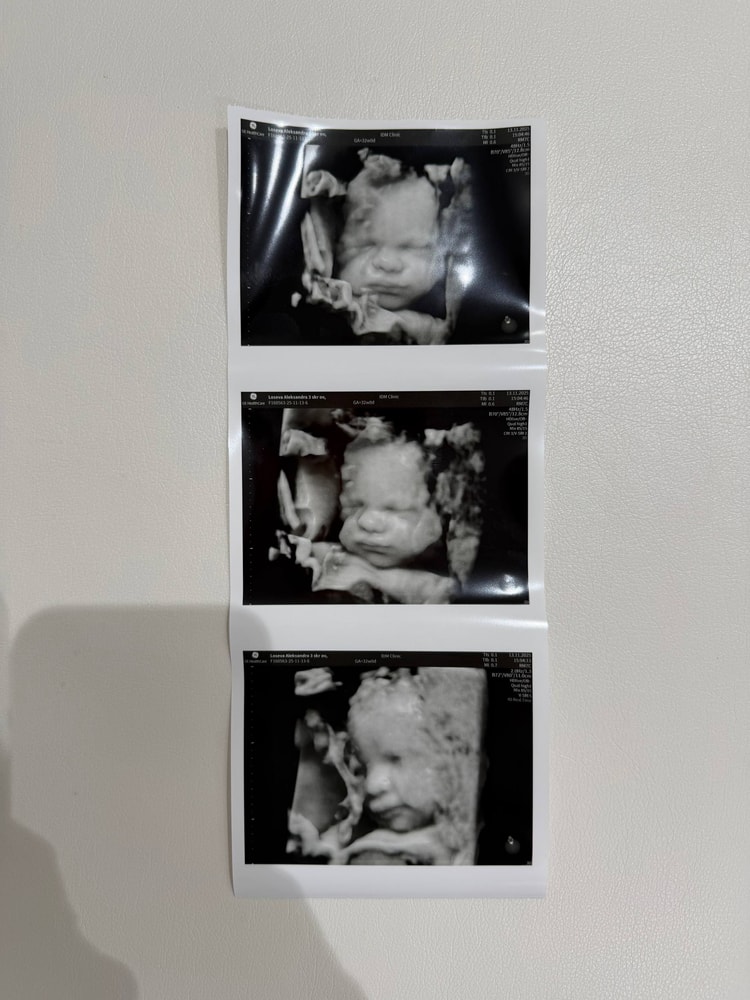

На часах: 35нед1д. Чувствую, как доча продолжает сидеть на попе. Йогиня, блин) И коленно-локтевая, и с боку на бок через живот, и бассейн. Мне что, на брейк нижний пойти?

ой, какая красиваяяя!!!!

"Мне что, на брейк нижний пойти?" - прикол)))))

главное-здоровая